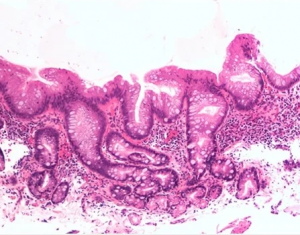

Φαρυγγολαρυγγική Παλινδρόμηση και οισοφάγος Barrett. Άνδρας ασθενής 50 ετών, προσήλθε στο ιατρείο μας στην Κοζάνη με βαριά χρόνια φαρυγγολαρυγγική παλινδρόμηση....